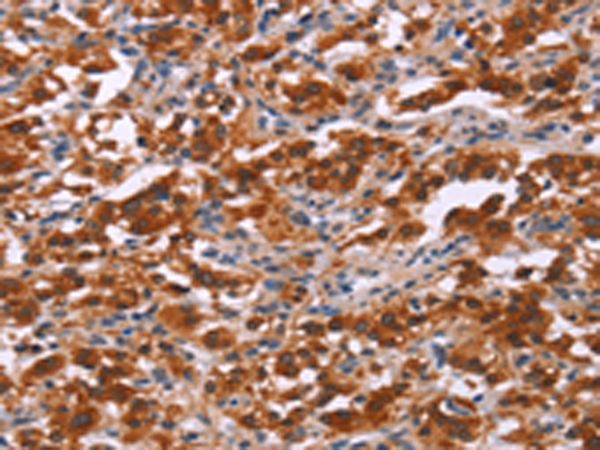

分类: 科研抗体货号: P04117别名: MMP25; MMP-24; MT5MMP; MTMMP5; MT-MMP5; MT5-MMP; MT-MMP 5应用: IHC反应种属: Human, Mouse, Rat